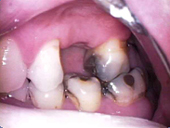

Ist der Zahnnerv durch Karies oder seltener, durch einen Unfall so geschädigt, dass er entfernt werden muss, wird eine Wurzelbehandlung notwendig. Dabei wird der Nerv entfernt, der Zahn bzw. die Zahnwurzel gereinigt und desinfiziert und danach mit einem oder mehreren Kunstharzstiften gefüllt. Er bekommt eine Wurzelfüllung.

Wird diese Behandlung mit der notwendigen Sorgfalt durchgeführt, kann der Zahn danach, wie jeder gesunde Zahn, weiter seine Arbeit verrichten. Allerdings wird häufig nach einer Wurzelbehandlung, zum Schutz des Zahnes, eine adhäsive Kunststoffversorgung oder seltener eine Überkronung notwendig.